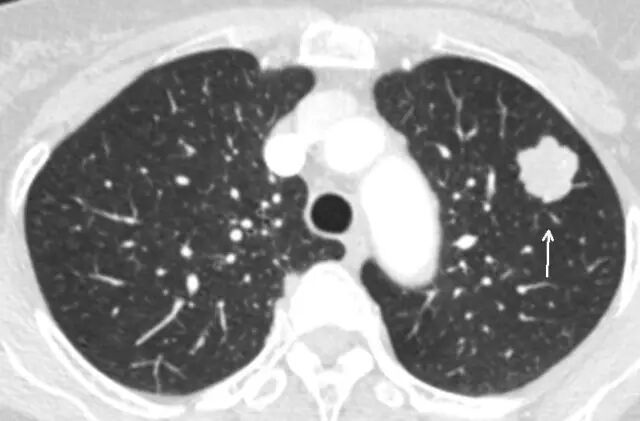

是指肺内直径≤3cm的密度增高影,通俗讲就是CT上黑色的肺里有小白点。>3cm的白色块状影称为肺肿块,通常肿瘤的可能性很大。

结节直径≤3cm

结节直径>3cm